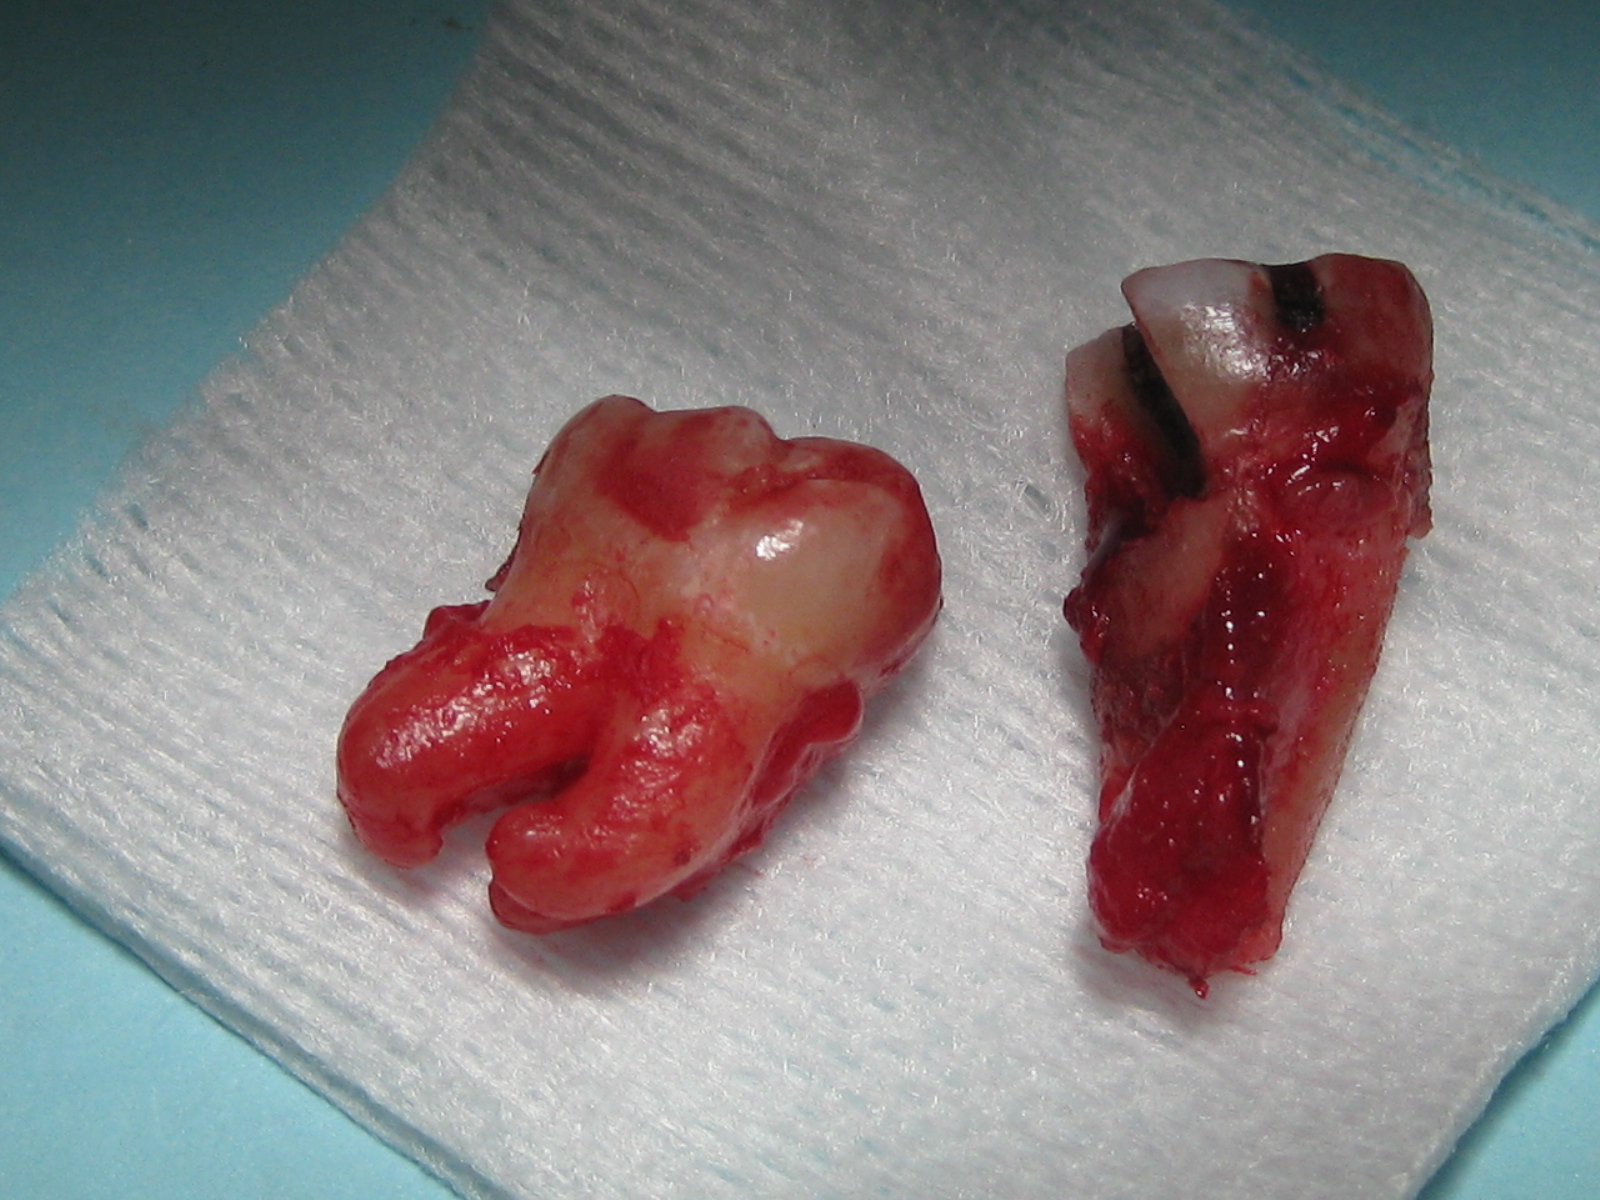

Our patient presented with a horrible tooth ache on her lower right molar.  It was hypersensitive to pressure. After a thorough exam, the tooth was fractured under the gums and couldn't be saved.  Our patient stated that this particular tooth had root canal treatment 3 separate times by 3 separate root canal specialists!  Everyone did everything they could to save the tooth, but it finally gave up and broke.  We carefully extracted the tooth and a bone graft was completed at the same time.  Immediate placement of the implant was not possible due to a horizontal defect of the bone and soft tissue.  After the bone graft healed, we placed the implant and delivered her new crown.  She is eating and living comfortably again!